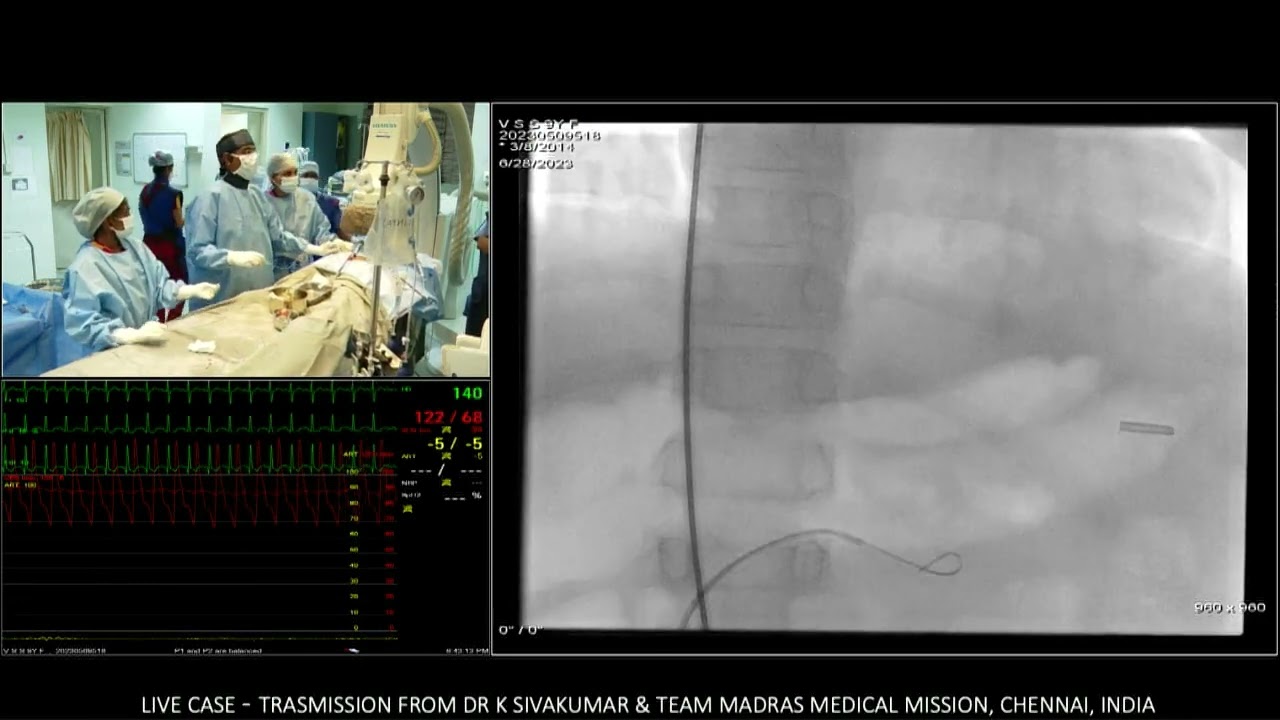

11/12 Sinus venosus atrial septal  defect  closure with covered stent exclusion